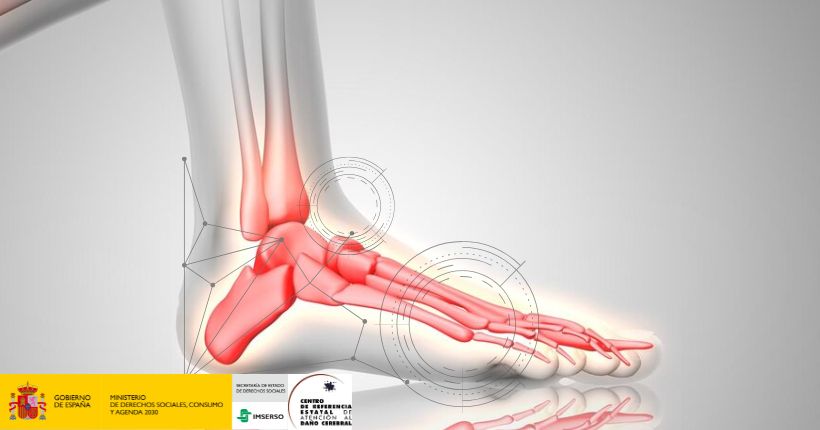

Entrenamiento robótico en la rehabilitación del tobillo para pacientes con ictus con pie caído: optimización de la intensidad y la frecuencia

Hoy en el blog queremos compartir el artículo Ankle rehabilitation robot training for stroke patients with foot drop: Optimizing intensity and frequency publicado en la revista NeuroRehabilitation. Introducción Las soluciones robóticas para la fisioterapia de la articulación del tobillo se han investigado ampliamente. Sin embargo, se desconocen la frecuencia e intensidad óptimas del entrenamiento para los pacientes cuando utilizan el robot de tobillo, lo que puede afectar al resultado de la rehabilitación. Objetivo El objetivo de este artículo fue explorar el protocolo óptimo para el entrenamiento robótico del tobillo para pacientes con ictus y pie caído. Metodología Los pacientes se dividieron aleatoriamente en cuatro grupos, de 9 personas cada uno. Recibieron entrenamiento combinado con robots de diferentes intensidades (baja o alta) con frecuencias (1 o 2 sesiones diarias). Cada sesión duró 20 minutos y todos entrenaron 5 días a la semana durante 3 semanas. Resultados Los resultados obtenidos tras 3 semanas de tratamiento fueron los siguientes: Todos los grupos mostraron una mejora en el rango de movimiento de dorsiflexión (movimiento articular que consiste en la flexión hacia arriba de una extremidad) de tobillo pasivo y activo (PROM y AROM) y en la evaluación de Fugl-Meyer para extremidades inferiores (FMA-LE) en comparación con el pretratamiento. Al entrenar al mismo nivel de intensidad, los pacientes que recibieron 2 sesiones diarias de entrenamiento mostraron una mejoría mayor en el PROM de dorsiflexión de tobillo que aquellos que recibieron 1 sesión diaria. En cuanto a la mejora en el AROM de dorsiflexión y la FMA-LE, los pacientes que recibieron 2 sesiones diarias de entrenamiento de alta intensidad mejoraron más que los pacientes con otros protocolos. Conclusiones En conclusión, el entrenamiento robótico de alta frecuencia y alta intensidad puede ser más eficaz para mejorar la disfunción del tobillo. Fuente Zhang Q, Wang Y, Zhou M, et al. Ankle rehabilitation robot training for stroke patients with foot drop: Optimizing intensity and frequency. NeuroRehabilitation. 2023;53(4):567-576. doi:10.3233/NRE-230173. Puede leer el artículo completo en el siguiente enlace o solicitarlo a través del correo: centro.recursos.ceadac@imserso.es